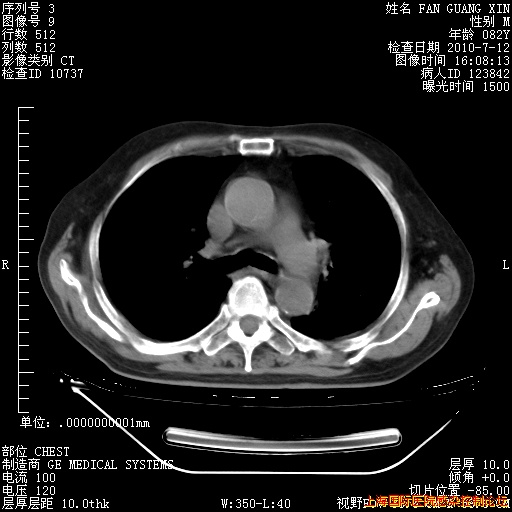

6月12日纵膈窗

今天复查CT

今天CT

整整相隔30天的肺部CT好像有所好转啊。甲强龙减量第3天,需要观察体温。